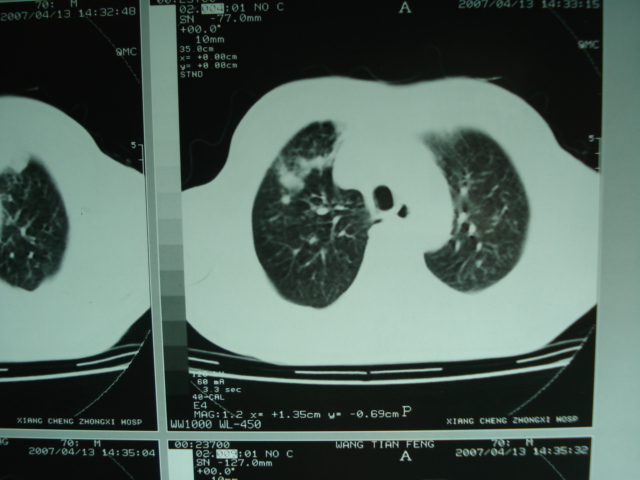

以下是引用狙击手在2007-4-18 20:17:00的发言:[br]原:2007/1/22号ct片:右肺上叶可见片状、云雾状高密度影,右肺上叶后段可见三角形高密度影,尖端指向肺门,右肺上叶后段支气管壁不规则增厚,管腔不规则增厚,纵隔未见肿大淋巴结.[br] 今ct:右肺上叶片状影增大,右肺上叶后段不张及右肺上叶后段支气管壁不规则增厚未见变化,右肺下叶背段支气管壁不规则增厚.[br] 如果考虑肺结核,但从临床证据看竟然没有一项支持肺结核,不知患者是否已经过正规抗结核治疗。没有的话,3个月了前后片看起来变化不大,似乎有不太符合肿瘤征象,不知患者是否抗炎治疗过,下叶支气管增粗还是要高度警惕,同意楼主意见,将常规病理,生化检查再做一遍。[br]

以下是引用狙击手在2007-4-18 20:17:00的发言:[br]原:2007/1/22号ct片:右肺上叶可见片状、云雾状高密度影,右肺上叶后段可见三角形高密度影,尖端指向肺门,右肺上叶后段支气管壁不规则增厚,管腔不规则增厚,纵隔未见肿大淋巴结.[br] 今ct:右肺上叶片状影增大,右肺上叶后段不张及右肺上叶后段支气管壁不规则增厚未见变化,右肺下叶背段支气管壁不规则增厚.[br] 如果考虑肺结核,但从临床证据看竟然没有一项支持肺结核,不知患者是否已经过正规抗结核治疗。没有的话,3个月了前后片看起来变化不大,似乎有不太符合肿瘤征象,不知患者是否抗炎治疗过,下叶支气管增粗还是要高度警惕,同意楼主意见,将常规病理,生化检查在做一遍。[br]